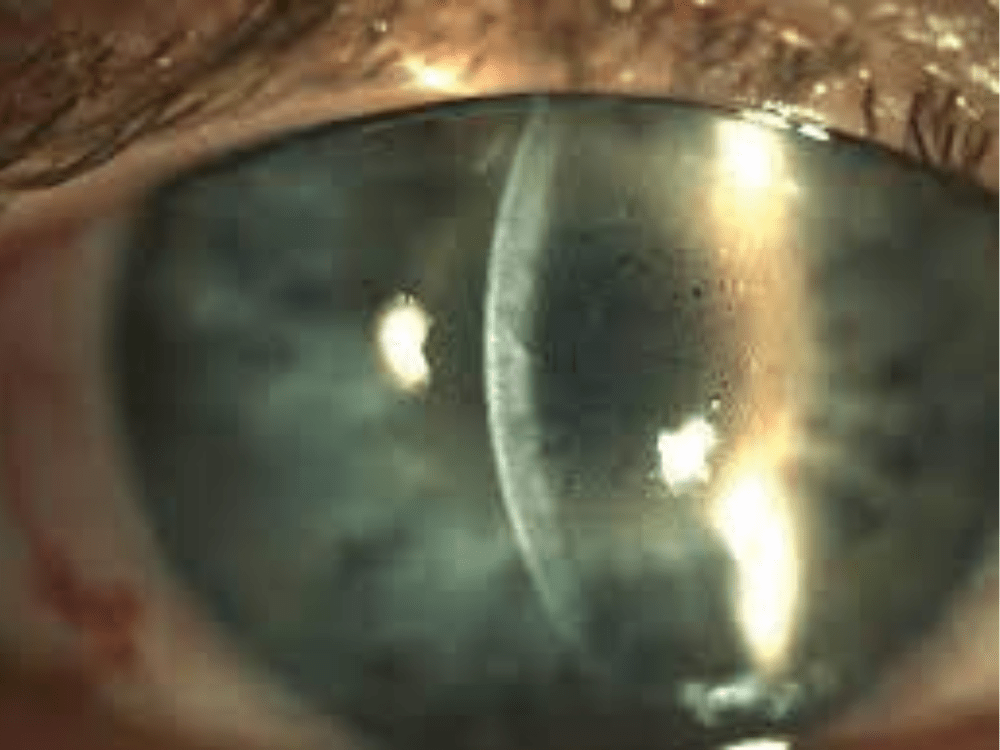

Fuchs' Dystrophy

Fuchs’ Dystrophy is a degenerative disease where the endothelial cells in the inner layer of the cornea gradually die off. This leads to fluid build-up in the cornea, causing swelling, cloudiness, and vision problems, especially in the morning. it is a common occurrence

Some cause severe visual impairment, while a few cause no vision problems and are discovered during a routine eye examination. Some of the most common corneal dystrophies include Fuchs’ dystrophy, keratoconus, lattice dystrophy, and map-dot-fingerprint dystrophy.

Asymptomatic dystrophies need no treatment Corneal transplant for vision in symptomatic patients.